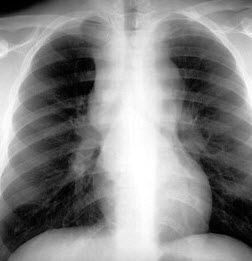

17、单项选择题

男,22岁,感胸痛且大汗淋漓就诊,X线检查如图,最可能的诊断是()

A.正常胸片

B.左肺肿瘤

C.左侧肺气肿

D.左侧气胸

E.支气管囊肿

18、判断题 中心型脊椎结核早期即引起椎间隙狭窄。